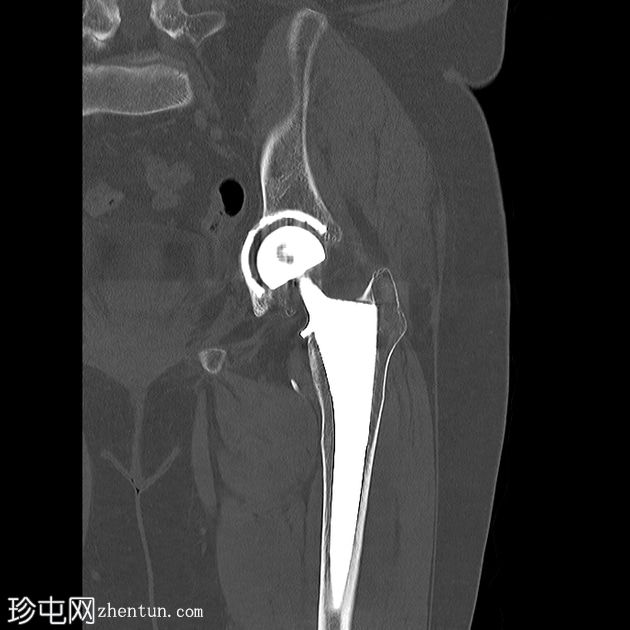

骨盆及左髋关节

双侧全髋关节置换术假体完整,无松动迹象。

左侧股骨大转子下区外侧皮质中断,侧位片显示最佳,提示假体周围骨折。